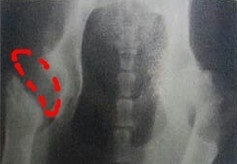

圖中所示紅線劃分出了股骨頭在髖臼內的股骨頭,大約只占股骨頭的1/4,屬于嚴重的髖關節發育異常